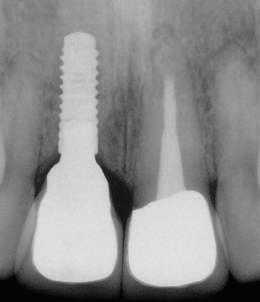

Pacientul a primit instrucțiunile de igienizare pentru noile restaurări protetice și programarea pentru controlul periodic, care se va suprapune cu continuarea planului de tratament. Bilanțul radiologic al cazului este evidențiat în fig. 10 a, b, c, d.

Narrow. Plasarea acestor bonturi încă din etapa chirurgicală a determinat vindecarea transgingivală și menținerea volumului țesuturilor dure și moi peri-implantare, datorită influențelor benefice pe care le-au generat calitatea conexiunii conice Morse, conceptele "one abutment–one time" și "platform switching" care caracterizează sistemul de implanturi folosit. Transferul platformei protetice de la nivelul implantar (osos) la cel gingival și absența ciclurilor de dez-/re-inserare au determinat absența contaminării microbiene suplimentare a conexiunii bont-implant, precum și realizarea mai facilă a etapelor de amprentare și de verificare a calității scheletului și restaurării finale. Amprenta în lingură deschisă "abutment-level" prezintă mai puține tensiuni comparativ cu cea "implant-level", la care bonturile de amprentă se înșurubează în implanturi. În aceste condiții, solidarizarea unui număr de până

la trei stâlpi de amprentă în lingură deschisă devine opțională. Testarea și verificarea pasivității au fost realizate atât la proba de schelet, cât și la proba finală a restaurării, prin aprecierea manuală a rezistenței la strângere a șurubului de fixare și prin evaluarea radiologică a adaptării piesei protetice pe pragurile de sprijin ale bonturilor intermediare. Intensitatea contactului proximal a fost evaluată după înșurubarea restaurării cu sprijin implantar la cuplul de forțe de 10Ncm și verificată cu ajutorul aței dentare, ținând cont de particularitățile parodontale ale implanturilor și dinților (anchiloză funcțională vs. parodonțiu de susținere).

Figurile 9 Aspect final în cavitatea orală al coroanelor mixte metalo-ceramice 34, 35 şi al protezei parţiale fixe metalo-ceramice cu sprijin implantar înşurubată; 10 Bilanţul radiologic al cazului: a. aspectul radiologic al re-tratamentului

la nivelul dinţilor 34, 35; b. radiografia realizată după inserarea implanturilor şi aplicarea bonturilor intermediare; c. verificarea adaptării scheletului metalic la nivelul platformelor bonturilor intermediare; d. restaurarea finală.